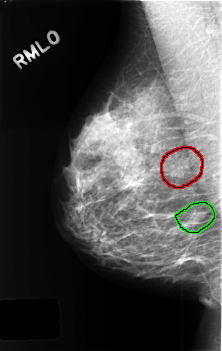

C_0437_1.RIGHT_MLO

FILE: C_0437_1.RIGHT_MLO.OVERLAY

TOTAL_ABNORMALITIES 2

ABNORMALITY 1

LESION_TYPE MASS SHAPE FOCAL_ASYMMETRIC_DENSITY MARGINS N/A

ASSESSMENT 3

SUBTLETY 3

PATHOLOGY BENIGN_WITHOUT_CALLBACK

TOTAL_OUTLINES 1

BOUNDARY

ABNORMALITY 2